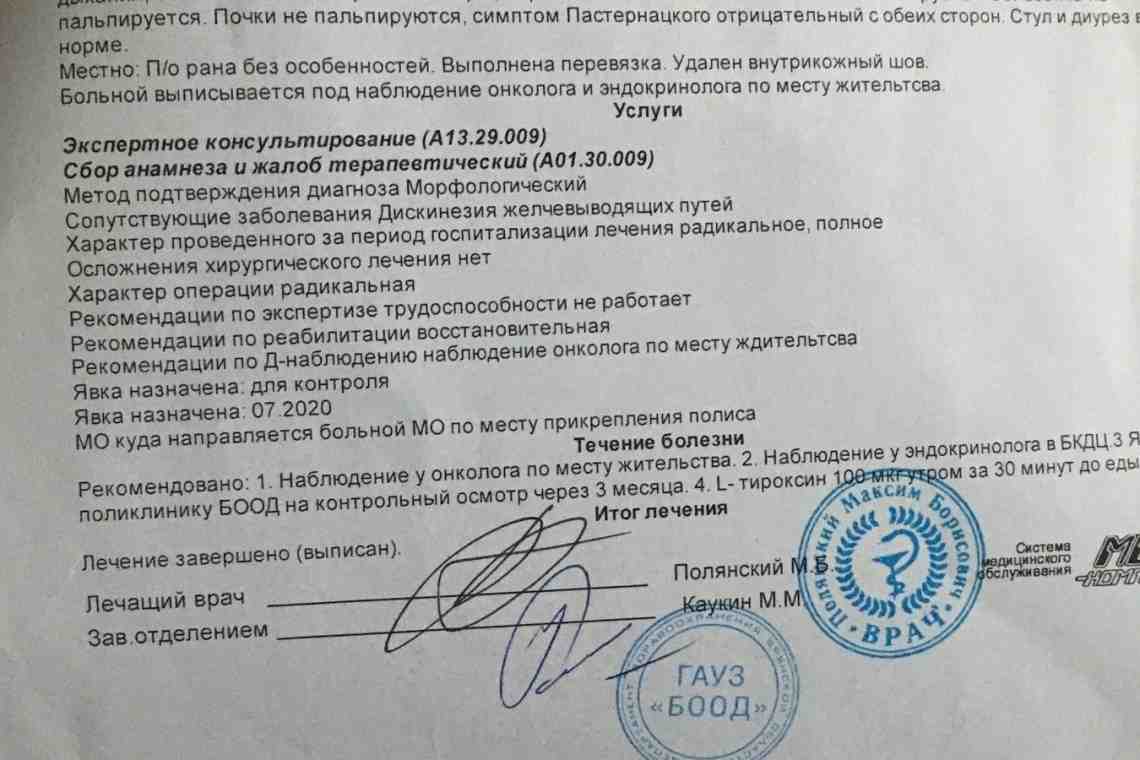

Здоровье женщин и его взаимосвязь с миром животных

Раздел: Другие животные